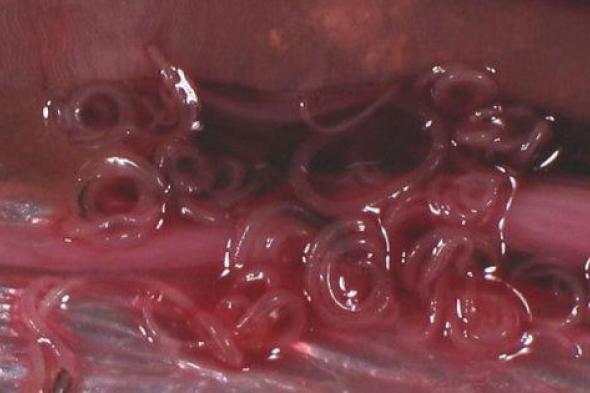

Así se ve el anisakis.WIKIMEDIA

Se han detectado los primeros casos de intoxicación por anisakis en pescado congelado, hasta ahora el método utilizado para eliminar sus efectos a la hora de ingerir pescado crudo.

España se sitúa después de Japón como el país con mayor número de intoxicaciones por anisakis, un parásito que se transmite a los seres humanos a través de la ingestión de pescados o cefalópodos contaminados y que provoca trastornos gastrointestinales y alérgicos.